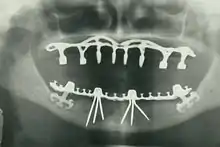

The modern movement of evidence-based dentistry calls for the use of high-quality scientific research and evidence to guide decision-making such as in manual tooth conservation, use of fluoride water treatment and fluoride toothpaste, dealing with oral diseases such as tooth decay and periodontitis, as well as systematic diseases such as osteoporosis, diabetes, celiac disease, cancer, and HIV/AIDS which could also affect the oral cavity. Other practices relevant to evidence-based dentistry include radiology of the mouth to inspect teeth deformity or oral malaises, haematology (study of blood) to avoid bleeding complications during dental surgery, cardiology (due to various severe complications arising from dental surgery with patients with heart disease), etc.

By nature of their general training, dentists, without specialization can carry out the majority of dental treatments such as restorative (fillings, crowns, bridges), prosthetic (dentures), endodontic (root canal) therapy, periodontal (gum) therapy, and extraction of teeth, as well as performing examinations, radiographs (x-rays), and diagnosis. Dentists can also prescribe medications such as antibiotics, sedatives, and any other drugs used in patient management. Depending on their licensing boards, general dentists may be required to complete additional training to perform sedation, dental implants, etc.

- Oral and maxillofacial radiology – The study and radiologic interpretation of oral and maxillofacial diseases.